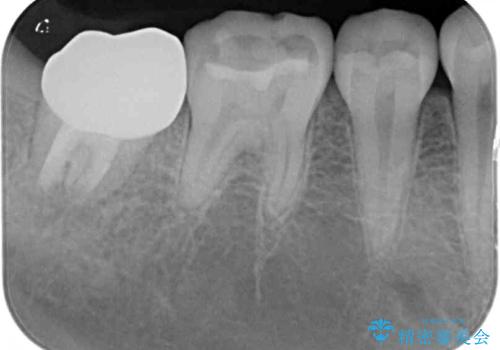

歯の高さが低く、かぶせものを安定して維持させることができないため、歯冠長延長術により歯の高さを増大させた上で、オールセラミッククラウンにて補綴することとしました。

歯の高さが増したことで、かぶせものが外れにくくなったことはもちろん、今まで無理と言われていたセラミッククラウンも装着でき、さらには歯間部の清掃性も向上したため、患者様には大変満足していただけました。